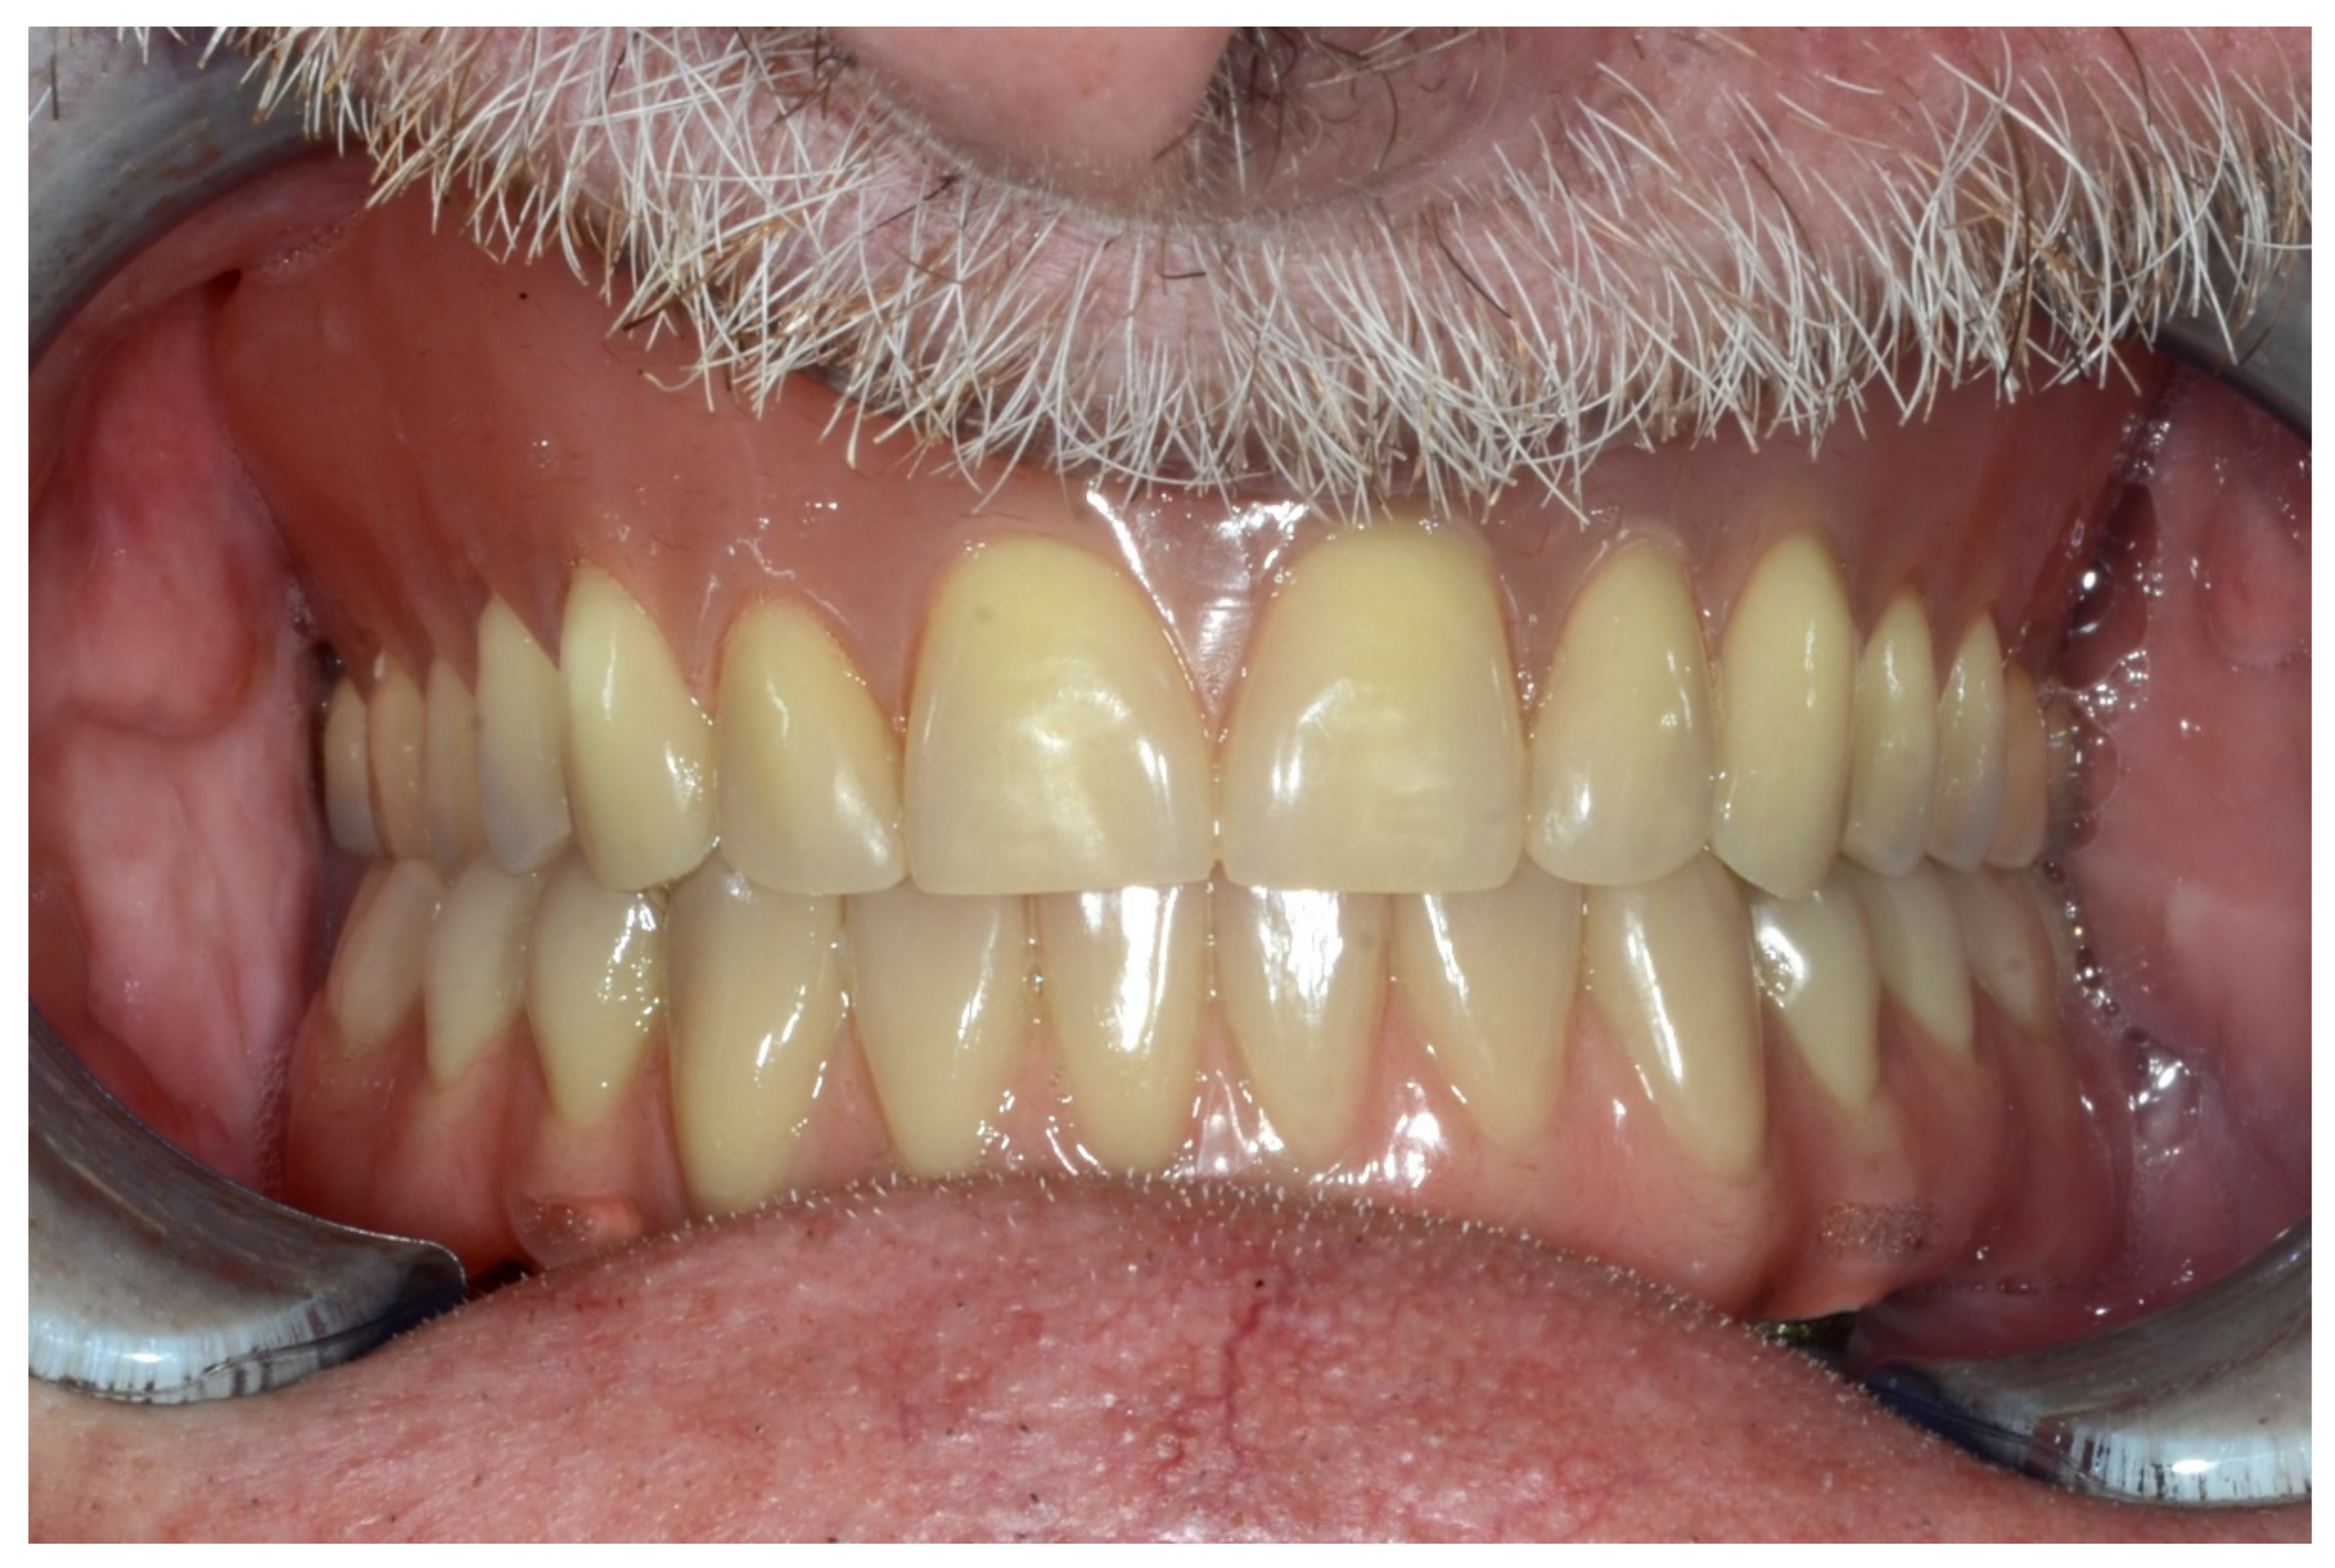

6.1.5. Postoperative (5-Years Follow-Up) Documentation:

A screw-retained provisional fixed prosthesis was used for 4 months to condition peri-implant mucosa, and in January 2019, the final prosthesis was installed. The occlusion was adjusted, and the patient received instruction for oral hygiene. A follow-up assessment at 5 years showed a stable cosmetic, biological and functional reconstruction (Figure 12, Figure 13 and Figure 14).

Figure 12.

Resting frontal close-up views.

Figure 13.

Smile frontal close-up views.